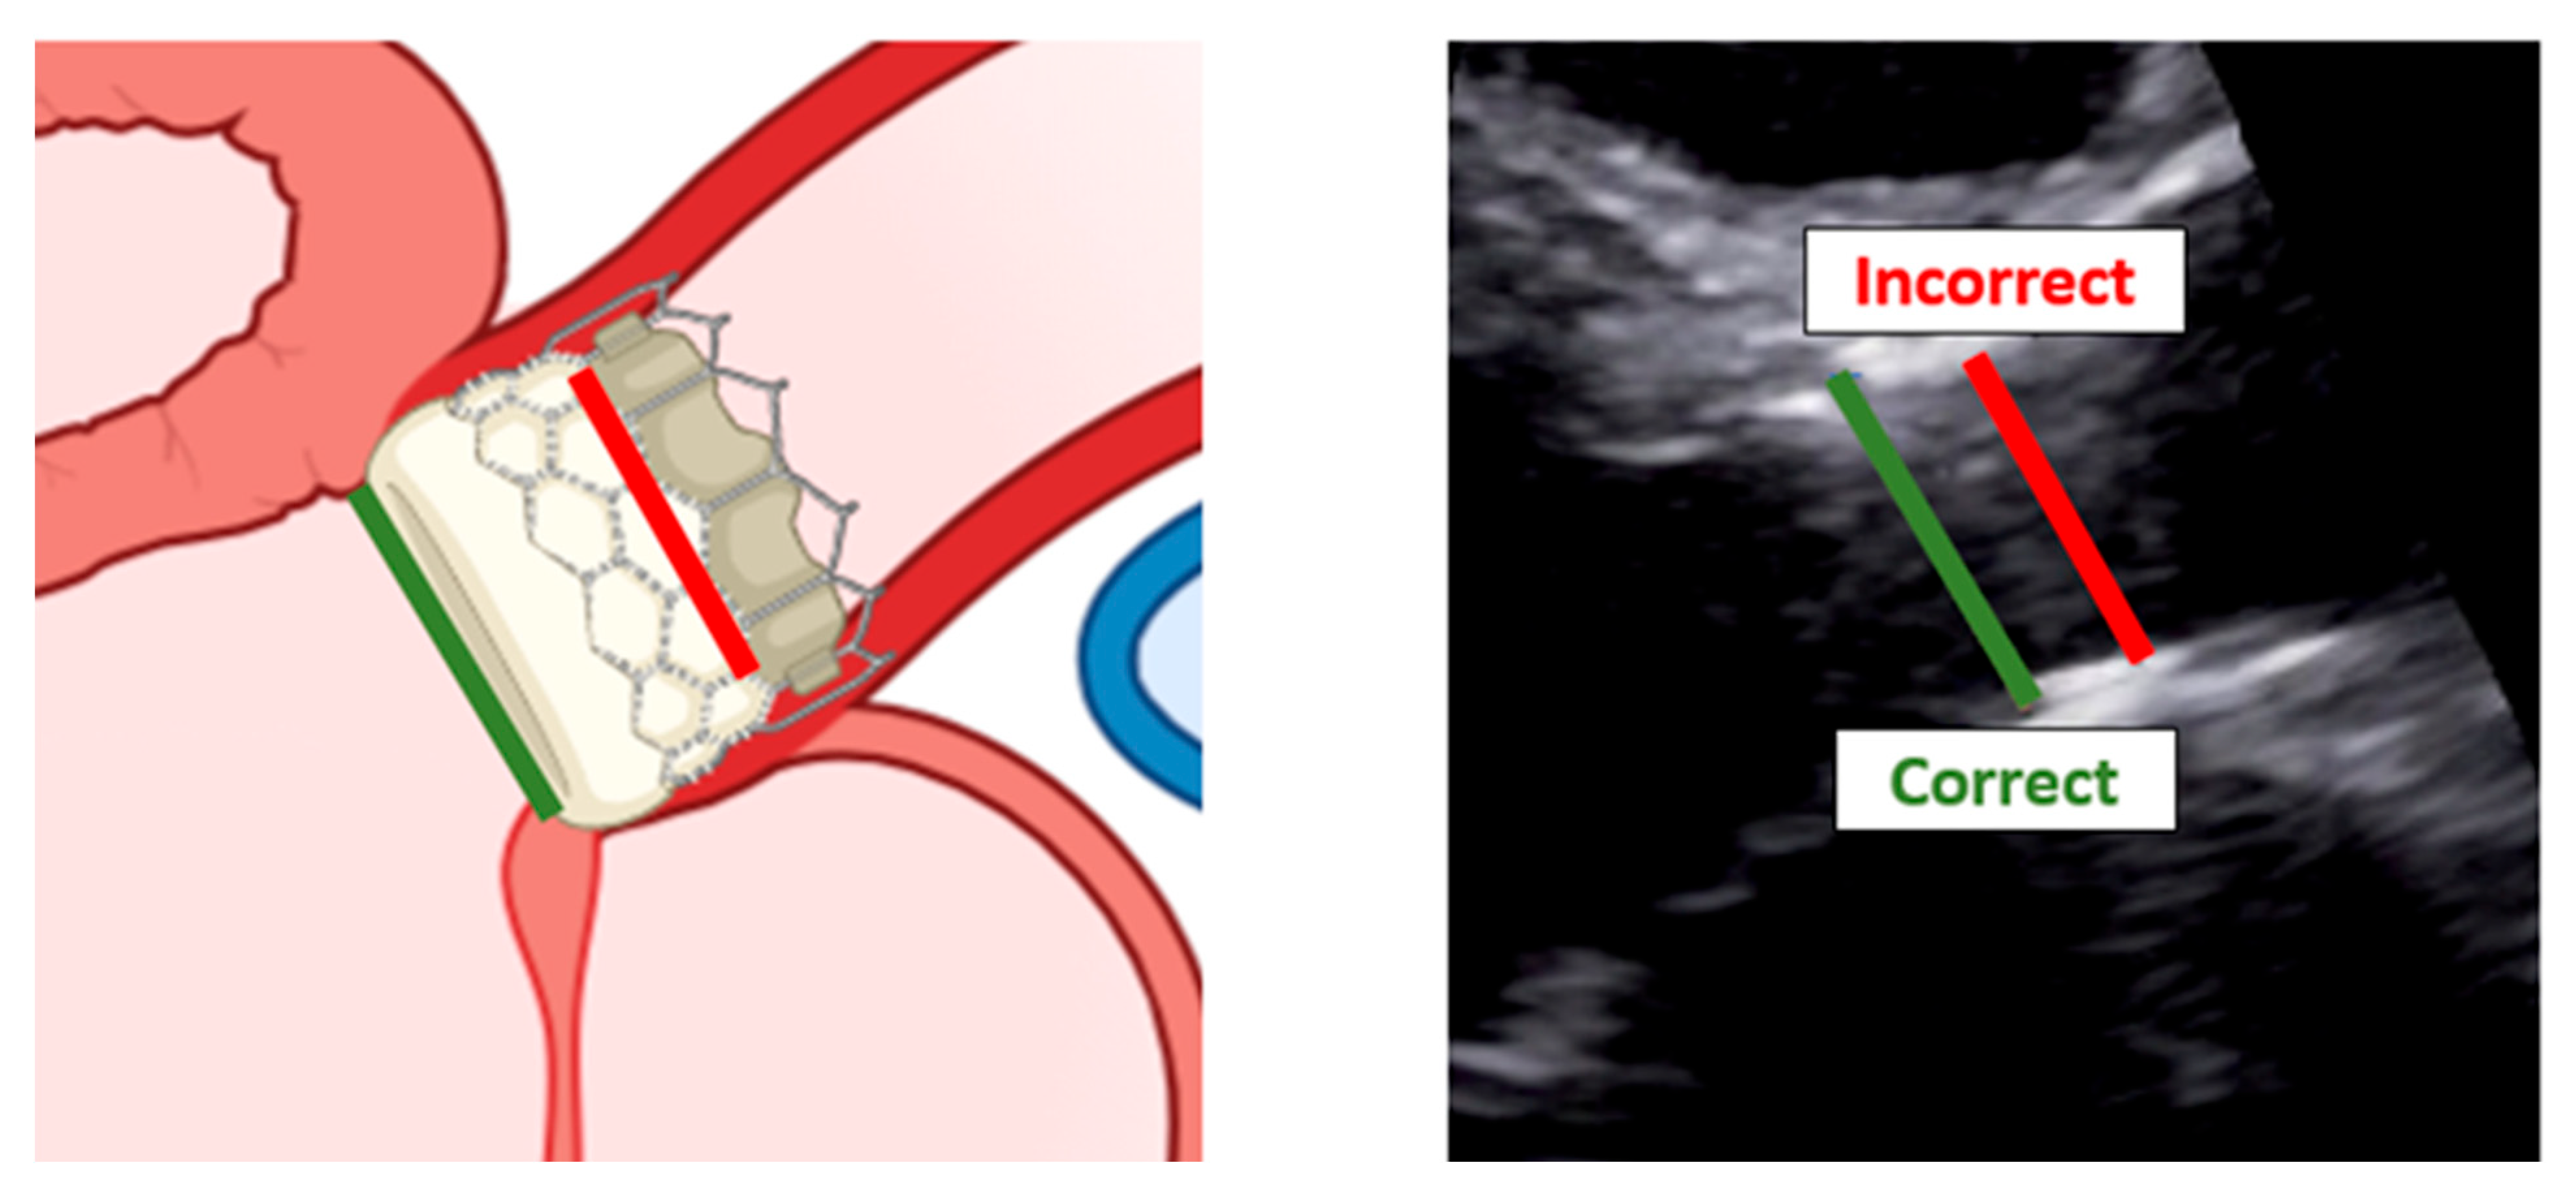

When assessing patients with aortic prosthesis, documentation of the size and type of valve should be marked on all echocardiograms. In addition, it is important to know, often for the aortic prosthesis, the level at which the prosthesis has been implanted: intra-annular, partially supra-annular, or wholly supra-annular. These aspects are important, since each valve type and size have their own normal ranges of values, such as peak velocity, peak gradient, mean gradient, and aortic valve effective orifice area (EOA). If repeat echocardiograms are being performed on a patient that has a prosthetic AV, the prior echocardiogram report should be reviewed to see what the AV measurements were, so any changes in function or abnormalities can be caught. To study aortic prosthesis, we will apply the same approach and calculations as we applied for a native valve. The prosthesis should be imaged from multiple views, with particular attention to (1) the opening and closing motion of the moving parts of the prosthesis (leaflets for bioprostheses and occludes for mechanical prostheses), (2) the presence of leaflet calcifications or abnormal echo density attached to the sewing ring, occluder, leaflets, stents, or cage, and (3) the appearance of the sewing ring, including careful inspection for regions of separation from the native annulus and for abnormal rocking motion during the cardiac cycle [50]. An important difference between the native aortic valve and prosthesis relies on the LVOT assessment. The LVOT diameter should now be measured at the ventricular side of the prosthesis, from outer edge to outer edge of the stent or ring just below the sewing ring for surgical prostheses or the stent for transcatheter bioprostheses [51] (Figure 11).

Recall that the LVOT pulsed-wave sample volume should be placed at the same level in the apical view that provides the best alignment with outflow through the device [52].

Figure 11. Correct measurement of left ventricular outflow tract in a patient with trans-catheter aortic valve implantation. Left: scheme of a left ventricular outflow tract. Right: a long-axis view with the implanted bioprostheses.